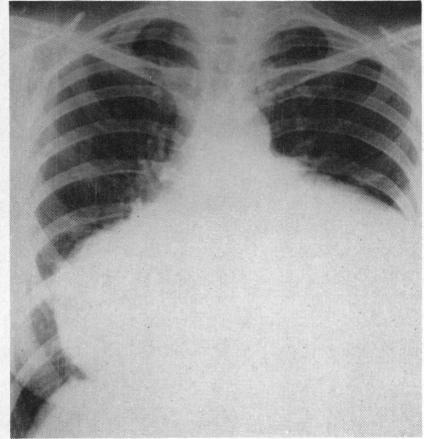

MASSIVE PERICARDIAL EFFUSION WITH CHOLESTEROL CRYSTALS TREATED BY PERICARDECTOMY.

Br Heart J. 1963 Nov;25(6):825-8. doi: 10.1136/hrt.25.6.825.